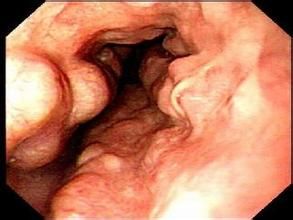

肝靜脈壓力梯度(HVPG)對食管胃靜脈曲張的發展、曲張靜脈出血的風險、門脈高壓的非曲張靜脈併發症的出現和死亡有預測價值。但由於HVPG的測量是一項有創性的操作,且由於技術及設備的限制,在國內並沒有廣泛開展,而且也難以普及性測量。但我們建議對於高危的患者(中、重度胃食管靜脈曲張、有出血史的患者)應行HVPG檢測,利於患者的治療及預後判斷。肝硬化和胃食管靜脈曲張患者的HVPG至少達10-12mmHg。靜脈曲張診斷的金標準是食管胃十二指腸鏡(EGD)檢查。其分類有兩種,一種是根據截斷直徑定量大小:小靜脈曲張指不於5mm,大靜脈曲張則指那些超過5mm者。第二種分類是分為3種:小、中或大。主要是通過半定量形態學判定(小的靜脈曲張一般被定義為食管黏膜表面上的較低程度的隆起靜脈,中等靜脈曲張被定義為占據不超過食管腔1/3的扭曲靜脈,大的靜脈曲張被定義為占據超過食管腔1/3的扭曲靜脈)。

1.纖維胃鏡檢查為最簡便而有效的檢查方法。出血停止後檢查雖然安全,但看不到活動的出血病灶;而正在出血時檢查,則湧出的血液往往掩蓋病灶,很難看清楚。Classen等總結美、英、德、瑞士和澳大利亞等國研究資料,認為早期胃鏡檢查85%~97%病例可明確診斷。國內學者積累的經驗認為,除休克患者、嚴重心肺疾病患者和極度衰竭的患者外,一般都能安全的接受胃鏡檢查。主張在出血48h內進行胃鏡檢查以判斷出血病灶的部位和性質。正常情況下,胃鏡觀察到食管下端以賁門為中心、直徑小於0.1cm的黏膜下血管,呈放射狀分布,血管勻稱不亂。門脈高壓症時,黏膜下血管增粗,呈串珠狀或蚯蚓狀隆起,食管下端近賁門部曲張的靜脈呈環狀隆起,隆起的曲張靜脈中心如見到約0.2cm大小的血泡樣隆起,預示即將出血。此外靜脈曲張已達食管中段,有2條以上的曲張靜脈,隆起的曲張靜脈向食管腔中突出、且在充氣後不能使之展平,曲張靜脈表面的黏膜充血、有櫻桃紅點等,均預兆即將出血。觀察胃底靜脈時,可將頭側墊高15°~20°,並經活檢孔插入沖洗管,沖洗乾淨,以便於觀察。胃靜脈曲張的程度雖然比食管靜脈曲張更重,但部位較深,覆蓋的黏膜變化不明顯,胃鏡檢查容易漏診。有時大的曲張靜脈可誤診為腫瘤,不大者又不易與黏膜皺襞區別。故對胃靜脈曲張的診斷,胃鏡不如X線;對食管靜脈曲張的檢查,則胃鏡優於X線。Okuda等曾比較了胃鏡和X線對胃靜脈曲張的檢查效果,46例經X線發現的胃靜脈曲張病例,胃鏡檢查能正確診斷者僅80%。我們發現有些患者X線檢查食管正常。胃鏡檢查都發現食管靜脈曲張。